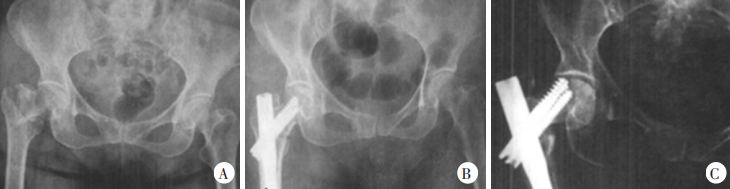

2024-04-24

Каковы факторы, вызывающие несостоятельность внутренней фиксации при лечении межвертельного перелома

Межвертельные переломы бедренной кости чаще встречаются у пожилых людей, чаще всего вызваны травмой, причем возраст ···

узнать больше